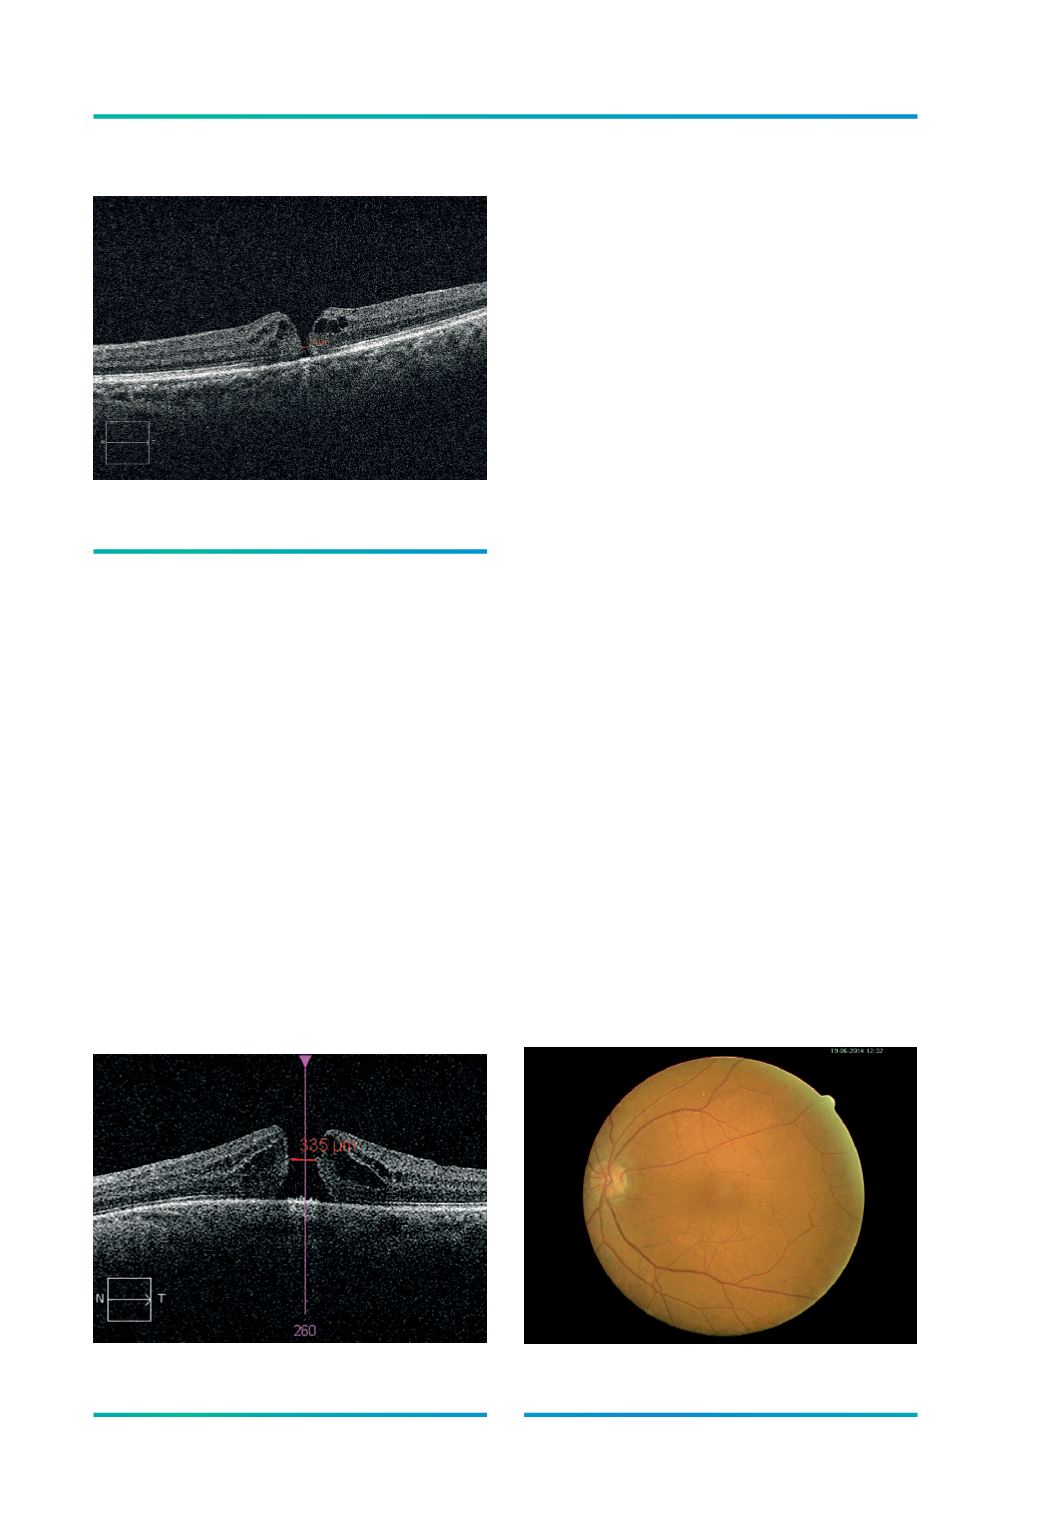

Figura 2.

OCT de micro-buraco macular (<150 µm).

Figura 3.

OCT de BM médio (250-400 µm).

Figura 4.

Retinografia de doente com BM pequeno.